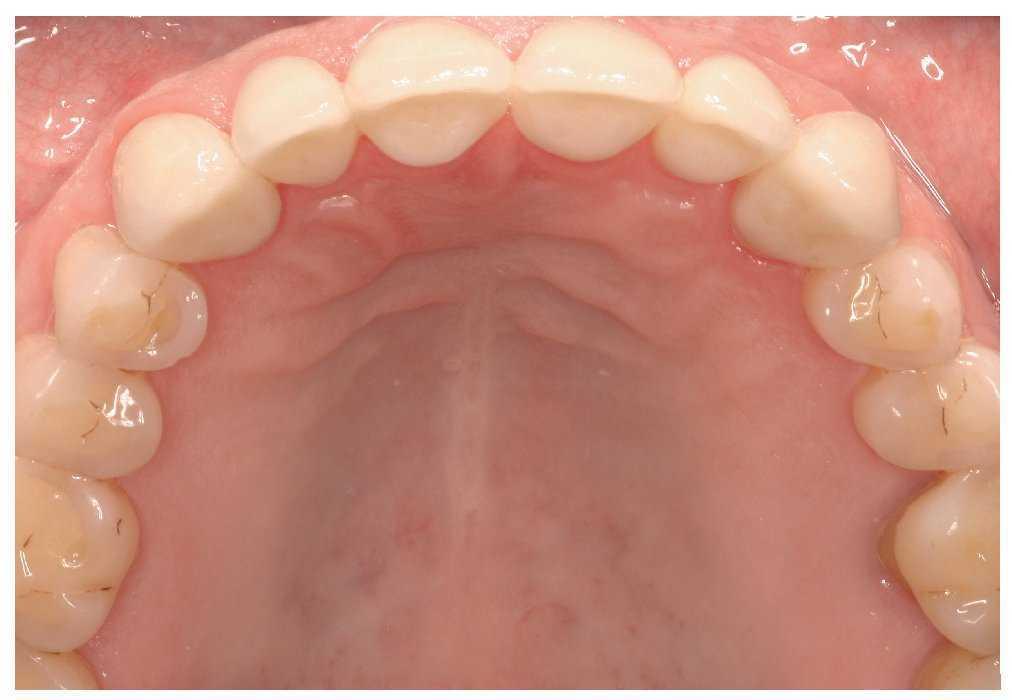

Después de controlar intraoralmente el ajuste, la estética y la función se prepararon las restauraciones para el cementado. Las caras internas de las restauraciones fueron chorreadas cuidadosamente (óxido de aluminio de 50 μm, Pluradent, Offenbach) a una presión de 2 bar65 y los restos de cemento provisional fueron eliminados de las superficies preparadas con copas de profilaxis (copas Prophy, Hager & Werken, Duisburgo, Alemania) sin pasta. Bajo un aislamiento relativo del campo llevado a cabo con aislantes de saliva (dry tips, Mölnlycke Health Care, Erkrath) y rollitos de algodón (rollos de algodón Luna de Roeko), se cementaron todas las restauraciones (figs. 18, 21 y 22) sin realizar un grabado ácido previo de la sustancia dentaria y utilizando un cemento de composite de polimerización dual autoacondicionador (Ralyx Unicem, 3M Espe). Una vez retirado el exceso de cemento se realizó un nuevo control intraoral de la oclusión.

Figura 21. Vista oclusal de la arcada superior con las restauraciones cementadas.

Figura 22. Restauraciones en la arcada inferior.